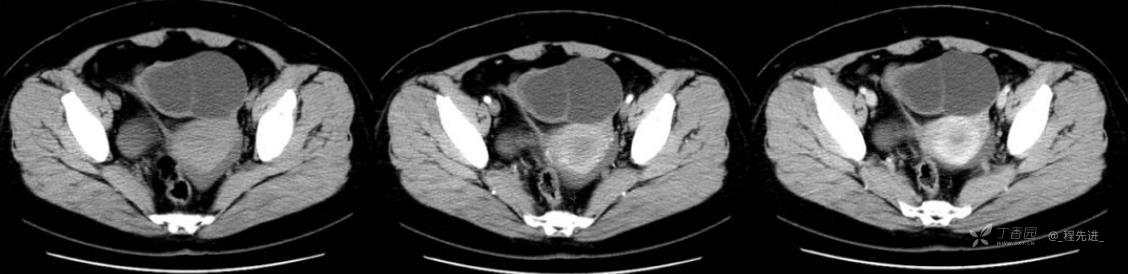

1月特别精彩病例|中老年女性,盆腔包块近半年持续增大【病理已公布】

患者年龄:53岁

简要病史:4年前体检时发现盆腔包块及子宫肌瘤,近半年复查盆腔彩超发现包块持续增大,近1年月经欠规律,伴腰、腹胀。

体格检查:宫颈举痛(+),子宫增大,质地中等,活动可,无压痛;右下腹轻压痛,无反跳痛,左侧附件区未扪及明显包块,无压痛。

阴式彩超:子宫约65*58*44mm大小,子宫肌层可见多个低回声块影,较大的为35*27mm(位于子宫前壁下段偏右侧壁),边界清,内回声欠均匀,后方回声衰减。考虑子宫多发肌瘤。子宫后壁可见一混合回声包块,大小约31*20mm,边界不清,内呈强弱回声,分布不均,考虑子宫腺肌瘤,其他疾患待删。子宫内膜厚6mm,宫颈可见多个囊性暗区,边界清,内透声好,后壁效应增强,较大的为15*11mm。子宫前方偏左侧可探及一大小89*75mm囊性肿块,边界清,壁薄光滑,内透声好,可见分隔光带